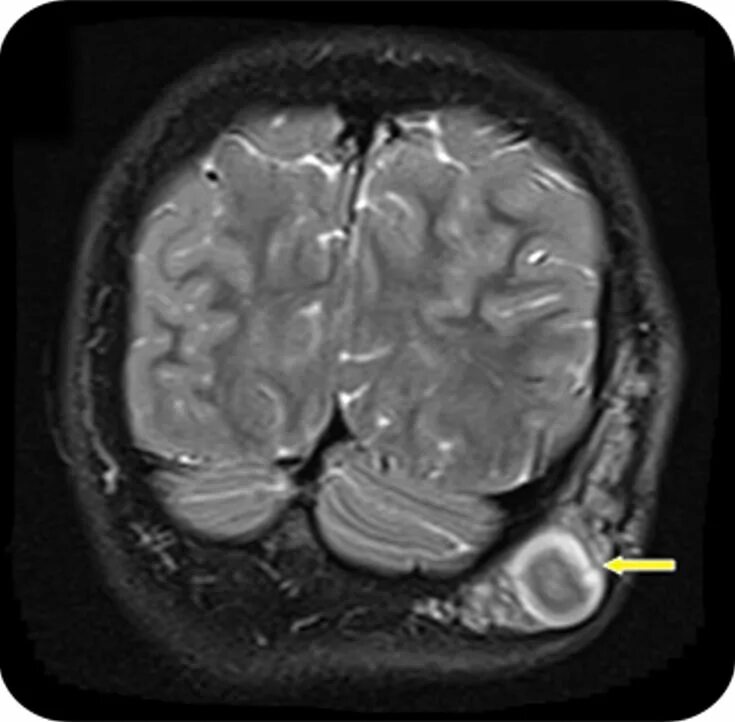

Нейрофиброматоз мрт